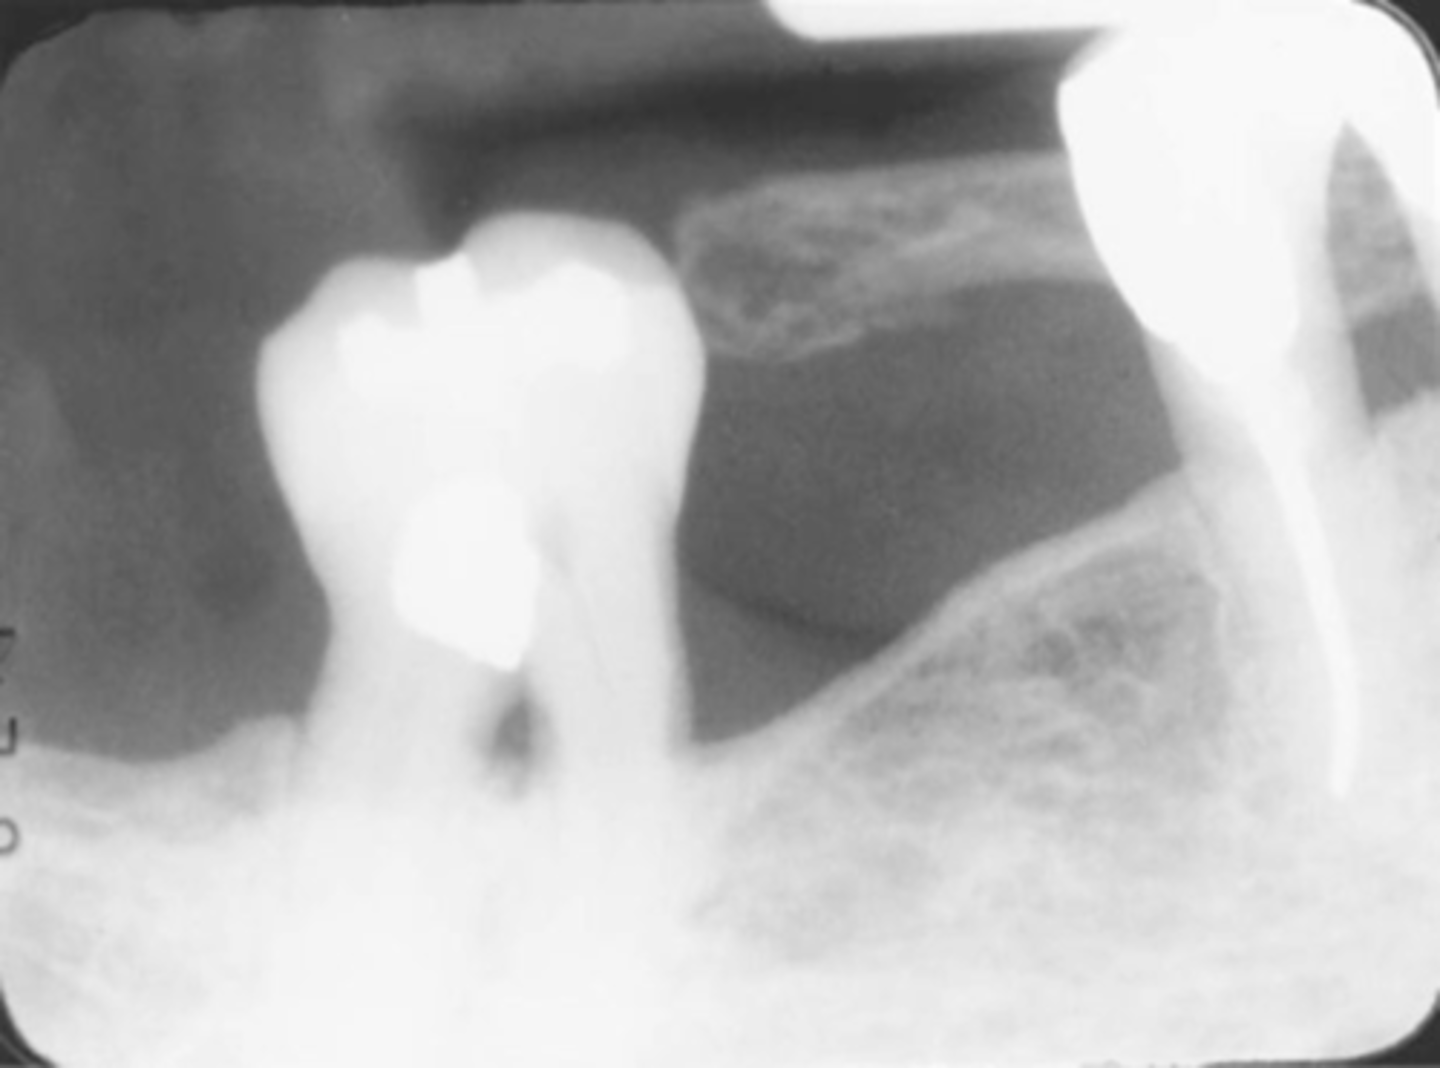

Incorrect Vertical Angulation-->Foreshortened Images

-Teeth appear short with blunted roots

-Vertical angulation was excessive, or too steep, resulting in images that are shorter than the actual teeth

-This occurs more often with the bisecting technique

-To prevent do not use excessive vertical angulation

Tube Head & PID-->Foreshortening of the image

-Excessive angulation (too steep) causing shortening of the anatomy of the teeth and/or cutting off occlusal or incisal edge.

Foreshortened image; Vertical angulation is too steep, Possible deflected film.